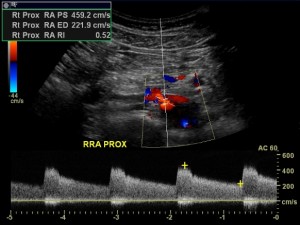

The most accurate non-invasive tools for defining renal artery stenosis are CTA and MRA. However, renal artery duplex ultrasound has added value. Duplex is cheap, non-invasive, does not involve radiation and is accurate as well. Duplex can offer physiologic information about the kidney in the form of the resistive index.

- Pre-procedural measures that suggest that renal artery stenting may be successful include significant renal artery stenosis (usually more than 70% as measured by duplex, CTA or MRA), rapid renal function deterioration (as opposed to chronic kidney dysfunction) and renal reserve (as suggested by a kidney that is more than 7 cm in length with a more or less preserved glomerular filtration rate). Another measure for renal reserve is the renal resistive index, although there is controversy regarding its usefulness. Also, an elevated brain natriuretic peptide as measured in peripheral blood may suggest that stenting may be successful.